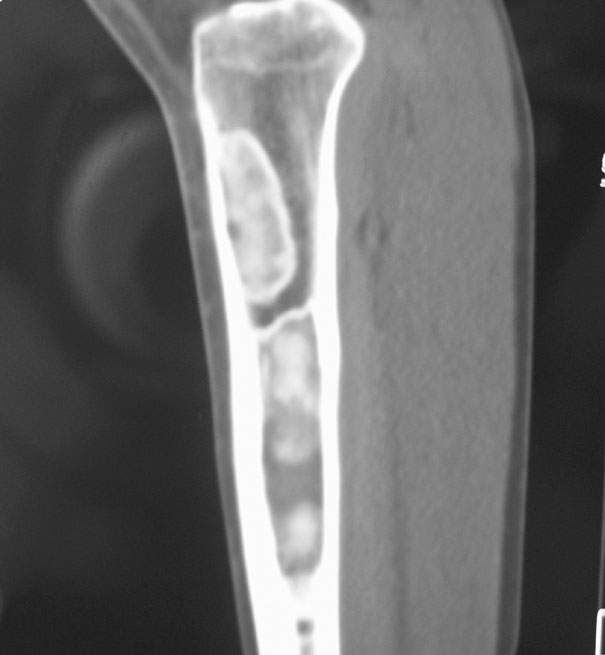

标题: CT19885:左胫骨上端肿瘤。 [打印本页]

标题: CT19885:左胫骨上端肿瘤。

男,20岁,医学院学生,11年前感左胫骨上端劳累后酸痛,曾由父母带到国内好几家有名望的医院诊治,但众说不一,所以基本上没有治疗。今年三月又开始出现症状,又到多家省级医院求治,但专家们的意见还是不能统一。各生化检查正常。mri考虑到胫骨上端良性血管瘤可能性大。ct考虑纤维瘤可能性大。请各位发表高见。

考虑胫骨多发性内生骨瘤。

胫骨多发性内生骨瘤可能。

考虑纤维类肿瘤,以骨化性纤维瘤可能性大。

考虑左胫骨良性骨肿瘤或骨肿瘤样病变(多发性内生骨瘤?骨纤维结构不良?)。

考虑胫骨多发性内生骨瘤可能。应该传骨窗。

左胫骨良性肿瘤或肿瘤样病变。骨纤?

考虑左胫骨良性骨肿瘤或骨肿瘤样病变(多发性内生骨瘤?骨纤维结构不良?)。骨梗死,纤维瘤。